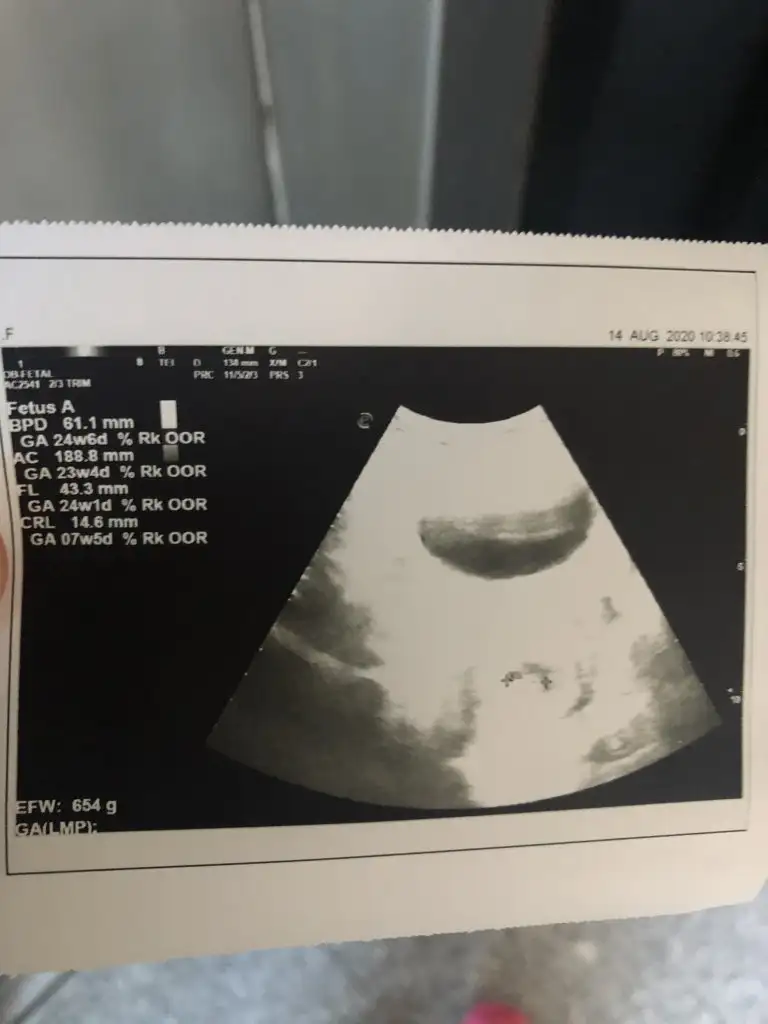

8+3 geç bu teori için yolk saç ne tarafta oluştuysa ona göre yorum yapmak lazım 6 veya 7 haftalık olmalıIkra meyra canım lütfen o güzel tahminlerinden bana da yapar mısın☺ 8+3 günlük karından usg

8+3 geç bu teori için yolk saç ne tarafta oluştuysa ona göre yorum yapmak lazım 6 veya 7 haftalık olmalı